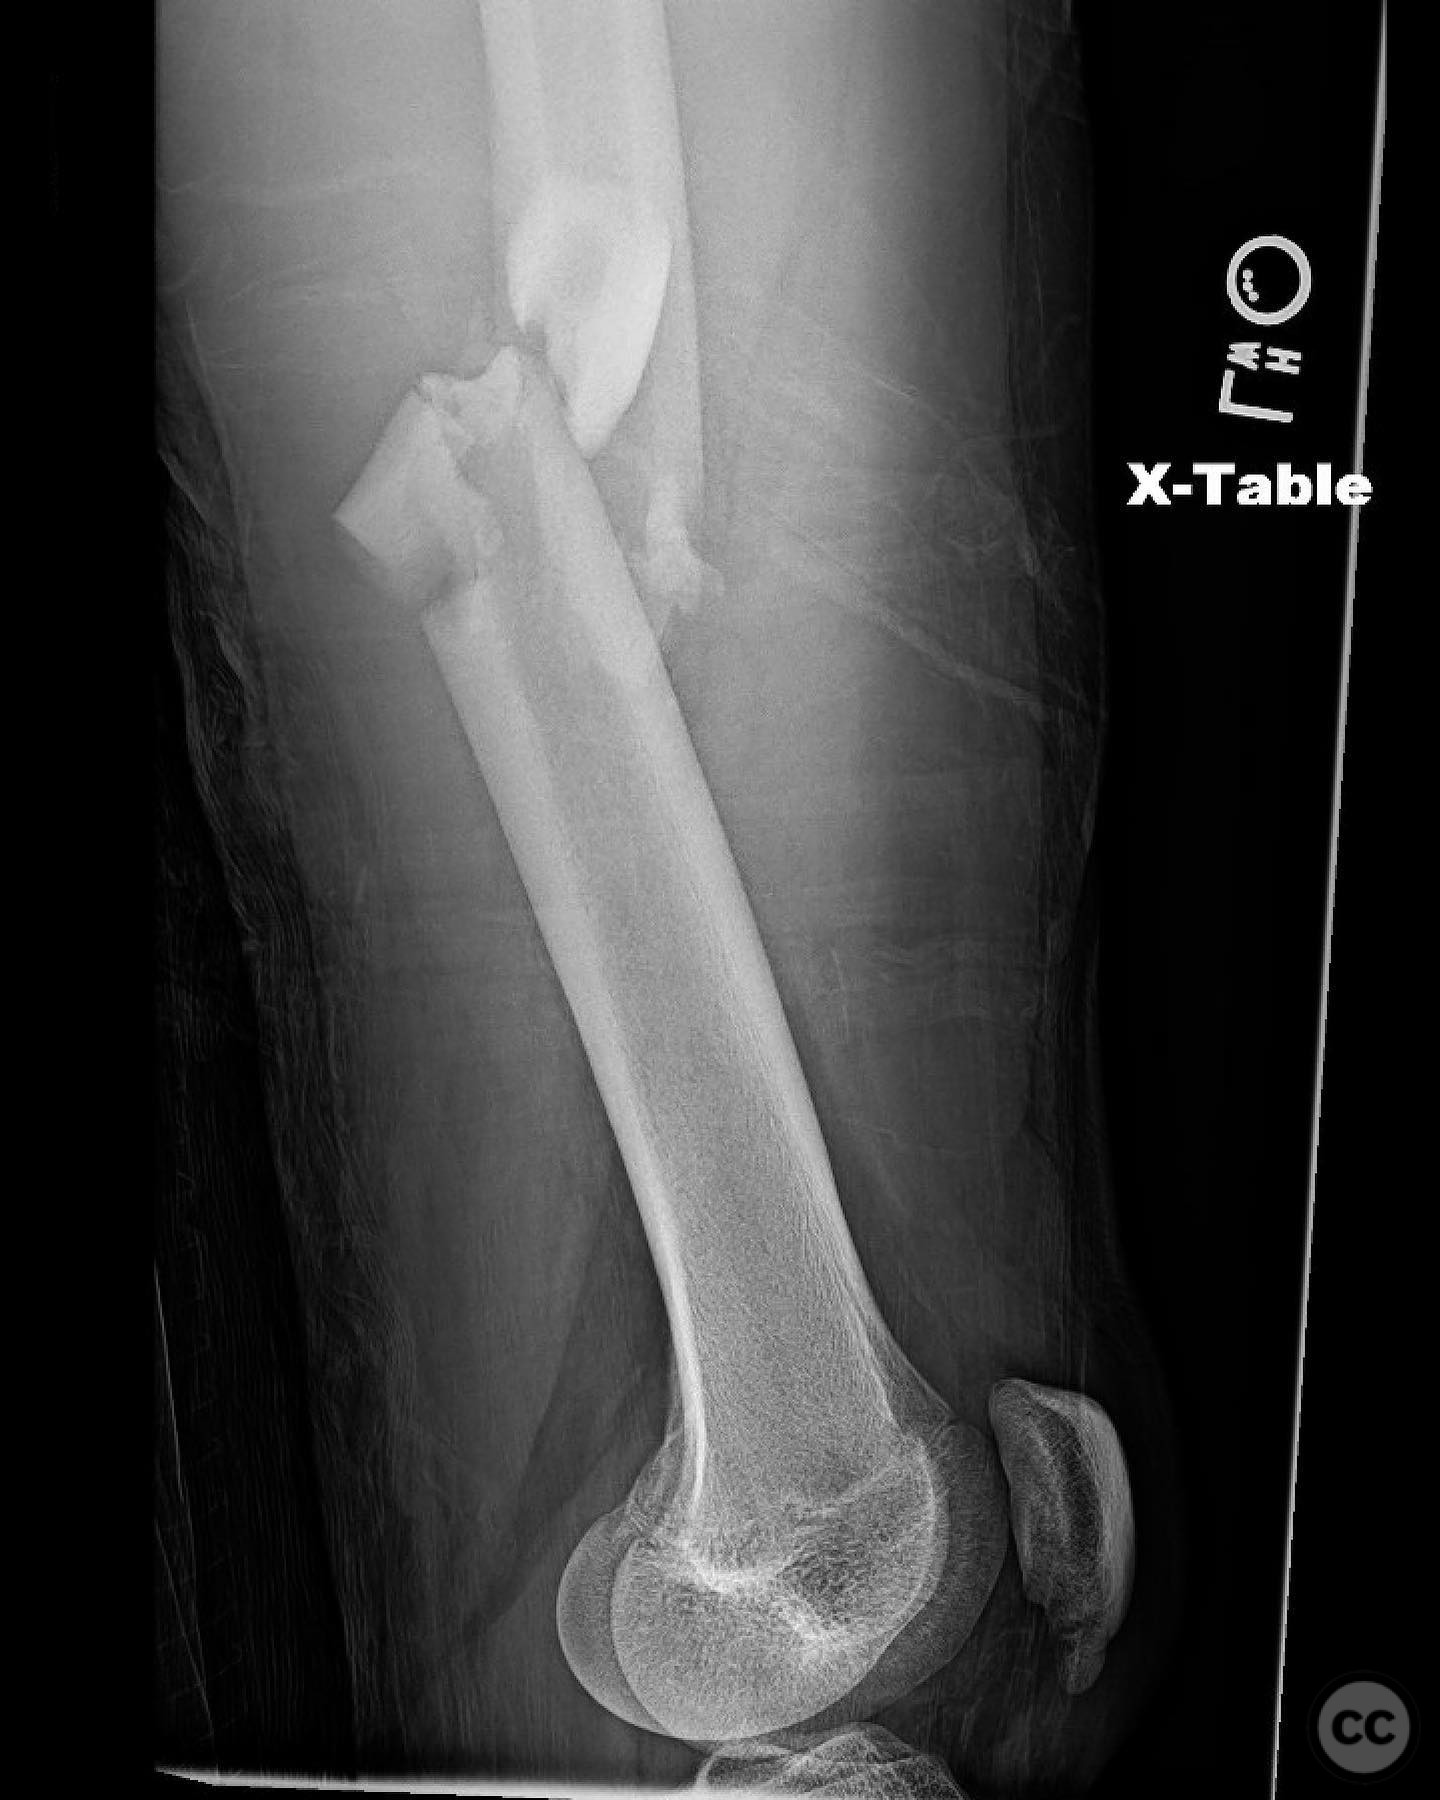

Clinical and radiological findings:  A 16-year-old male sustained a comminuted diaphyseal femur fracture after a 50-foot fall while rock climbing. The patient presented with multiple injuries but was well resuscitated and cleared for surgical treatment of the femur fracture within 24 hours. The injury was closed, with no neurological or vascular compromise noted.

Planning remarks:  The preoperative plan involved an open reduction and internal fixation (ORIF) due to the complexity of the fracture and the presence of a large incomplete napkin ring segment that could not be managed with closed nailing techniques. The anatomical approach was planned through a lateral incision to allow direct access to the fracture site for reduction and fixation.

Anatomical surgical approach:  A lateral approach to the femur was performed, involving an incision along the lateral aspect of the thigh. Subperiosteal dissection was carried out to expose the fracture site while preserving as much periosteum as possible. Care was taken not to disturb the medullary hematoma, and reamings were collected for later use in grafting.